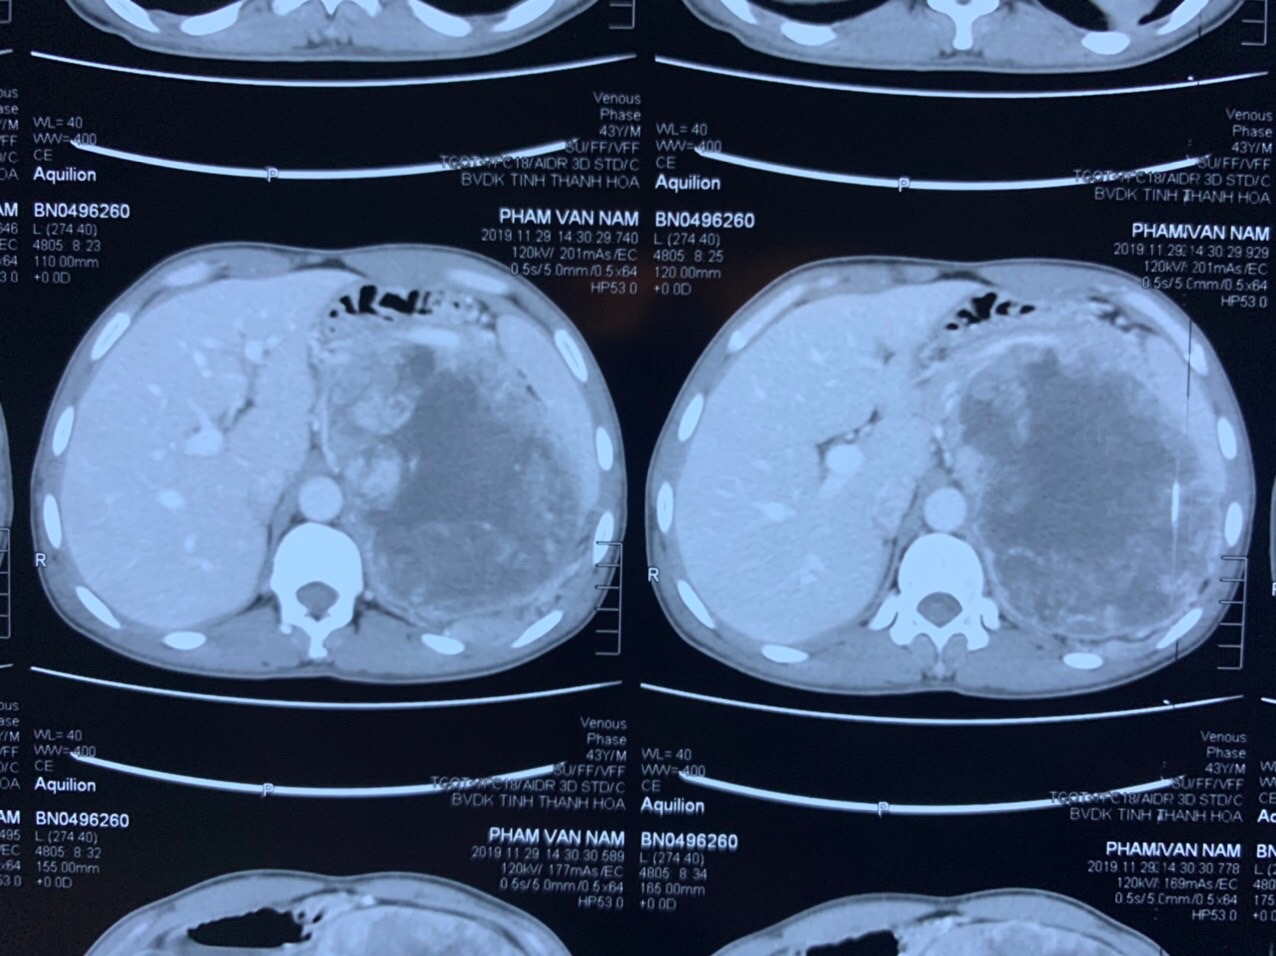

Hình ảnh khối u tuyến thượng thận trong cơ thể qua hình ảnh CT

Bệnh nhân đã được nhanh chóng làm các thủ tục nhập viện. Qua thăm khám lâm sàng cùng với các kết quả xét nghiệm, siêu âm, chụp CT, bệnh nhân đã được chẩn đoán u tuyến thượng thận trái, kích thước lớn và có chỉ định phẫu thuật để cắt bỏ khối u.

Tiến sĩ – Bác sĩ Trương Thanh Tùng – Trưởng phòng Kế hoạch tổng hợp – Phó Trưởng khoa Ngoại Tiết niệu – Trưởng kíp phẫu thuật cho bệnh nhân nhận định: “Đây là một trường hợp phẫu thuật khó vì có khối u to, kích thước lớn trên 10cm chèn ép đè đẩy thận trái xuống dưới và xâm lấn vào các cơ quan lân cận như cơ hoành và màng phổi trái …, tăng sinh mạch máu nhiều nên không thể tiến hành phẫu thuật nội soi. Quá trình phẫu tích khối u phải đối mặt với nhiều nguy cơ như tăng huyết áp, chảy máu, tổn thương động mạch chủ, động mạch lách và các tạng lân cận …Do đó phẫu thuật mở đòi hỏi phải được tiến hành tại phòng mổ có trang thiết bị y tế hiện đại, đồng bộ; kíp phẫu thuật viên và bác sĩ gây mê phải có trình độ chuyên môn cao và giàu kinh nghiệm, thao tác chuẩn xác, kiểm soát tốt huyết áp và các tai biến trong và sau mổ, đảm bảo an toàn cho bệnh nhân.”